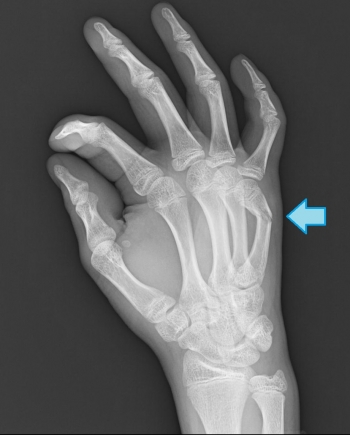

ËöÀá¹ü¹üÀÞ

»Ø¹ü¤ÎÃæ¤Ç¤â³°½ý¤ò¼õ¤±¤ëµ¡²ñ¤¬¤â¤Ã¤È¤â¿¤¯¡¢¼êÁ´ÂΤιüÀÞ¤ÎȾʬ°Ê¾å¤òÀê¤á¤ë¡£

¤â¤Ã¤È¤âÉÑÅ٤ι⤤»Ø¤Ï¡¢Ãæ»Ø¡¢¼¡¤ËÊì»Ø

ľã³°ÎϤˤè¤ë¤â¤Î¤¬Â¿¤¤¤¬¡¢ÆÍ¤­»Ø¤Ê¤É¤Î²ðã³°ÎϤÇȯÀ¸¤¹¤ë¤³¤È¤â¡£

¿¼»Ø¶þ¶Ú秤ÎÉÕÃåÉô¤Ë¤è¤ê¹üÊÒž°Ì¤¬ÊѤï¤ë¡£

¥Þ¥ì¥Ã¥È¥Õ¥£¥ó¥¬¡¼¡Ê¥Ï¥ó¥Þ¡¼»ØÊÑ·Á¡Ë

¥Þ¥ì¥Ã¥È¥Õ¥£¥ó¥¬¡¼¤Ï¡¢Ìîµå¡¢¥Ð¥ì¡¼¥Ü¡¼¥ë¤Ê¤É¤Îµåµ»¤ÎÃæ¤Ç¡¢ÆÍ¤­»Ø¤ò¤·¤ÆÈ¯À¸¤¹¤ë¡£

¥Ù¡¼¥¹¥Ü¡¼¥ë¥Õ¥£¥ó¥¬¡¼¡¢¥É¥í¥Ã¥×¥Õ¥£¥ó¥¬¡¼¤È¤â¸Æ¤Ð¤ì¤ë

¥Þ¥ì¥Ã¥È¥Õ¥£¥ó¥¬¡¼¤ÎʬÎà

­µ·¿¡¡½ª»ß秤ÎÃÇÎö

­¶·¿¡¡½ª»ß秤ÎÄä»ßÉô¤Ç¤ÎÇíÎ¥¹üÀÞ

­··¿¡¡ËöÀá¹ü¤ÎÇØÂ¦´ØÀáÌ̤ιüÀÞ

³§¤µ¤ó¡¢ÆÍ¤­»Ø¤Ï°ìÅ٤Ϥ·¤¿¤³¤È¤¬¤¢¤ë¤È»×¤¤¤Þ¤¹¤¬¡¢¤½¤³¤Ë¤Ï¹üÀޤ⤷¤Æ¤¤¤ë²ÄǽÀ­¤¬¤¢¤ê¤Þ¤¹¡£

Áá´ü¤Ë¥ì¥ó¥È¥²¥ó¤ò»£¤ê¤Þ¤·¤ç¤¦¤Í